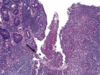

What are the three characteristic symptoms associated with the attached finding of a 40 y/o white male?

Whipple disease - note the distended foamy macrophages in lamina propria that contain T. whippelii.

On inspection you note the distended foamy macrophages in the lamina propria of this image, and you know that this, combined with the patients weight loss, diarrhea and polyarthritis means the patient has?

Which means we are looking at what part of the GI tract that this organism commonly infects?

What stain have you used to deted these T. whippleii?